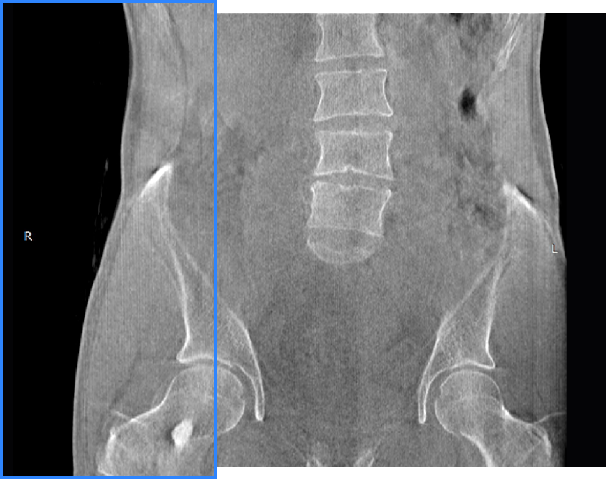

髖關(guān)節(jié)

支持雙腿或雙側(cè)髖關(guān)節(jié)掃描 | 方便對比,降低漏診誤診

FOV 250mm

FOV 350mm